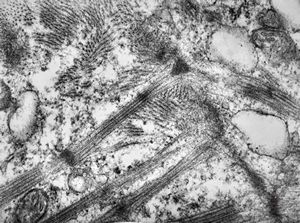

M,47y. | hypertrophic cardiomyopathy - left ventricle-crossing of myofilaments can also be caused arteficially with bioptom